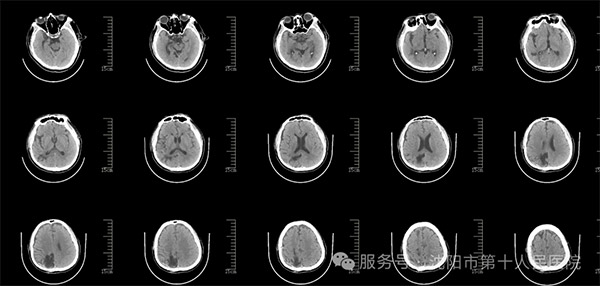

在修补手术时,神经外科医生和家属商讨后经同意最终决定采用当前最前沿的3D打印PEEK材料进行修补手术。手术前对患者进行头颅三维CT检查,根据患者CT数据进行三维重建,利用3D打印技术制作出与颅骨缺损完美匹配的植入物,最大程度还原原有颅骨的形态与曲率。最终在医患双方的共同努力下,手术顺利完成。术后,患者头颅恢复原貌,塌陷的头皮鼓起来,圆润饱满,匀称美观,几与受伤前无异。患者及家属对手术效果十分满意,并对医护人员的精湛医术和周到服务表示衷心感谢。

修补术后影像资料